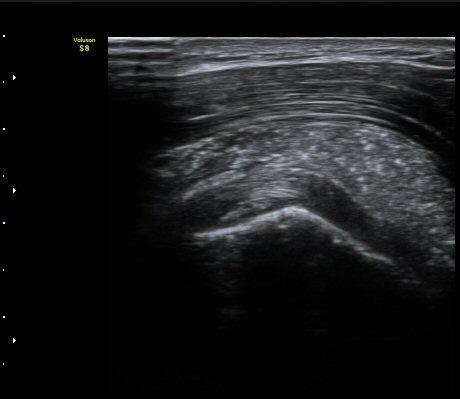

ÃÊÀ½ÆÄ °Ë»ç

À̵ιڱ٠Ⱦ´Ü¸é°Ë»ç¿¡¼­ Á¡¾×³¶³» °í¿¡ÄÚ ¼®È¸È­ À½¿µµéÀÌ °üÂûµÊ(±×¸² 1, 2, 5)

¿ÜȸÀüÀÇ Á¦ÇÑÀ¸·Î °ß°©ÇϱٰÇÀÌ ¼öÆòÀ¸·Î °üÂûµÇÁö ¸øÇϰí À̵ιڱ٠ǥÃþ¿¡

¼®È¸È­ À½¿µÀÌ °üÂûµÊ(±×¸² 3)

À̵ιڱ٠Á¾´Ü¸é°Ë»ç¿¡¼­µµ Á¡¾×³¶³» ¼®È­È­ À½¿µÀÌ °üÂûµÊ(±×¸² 4).